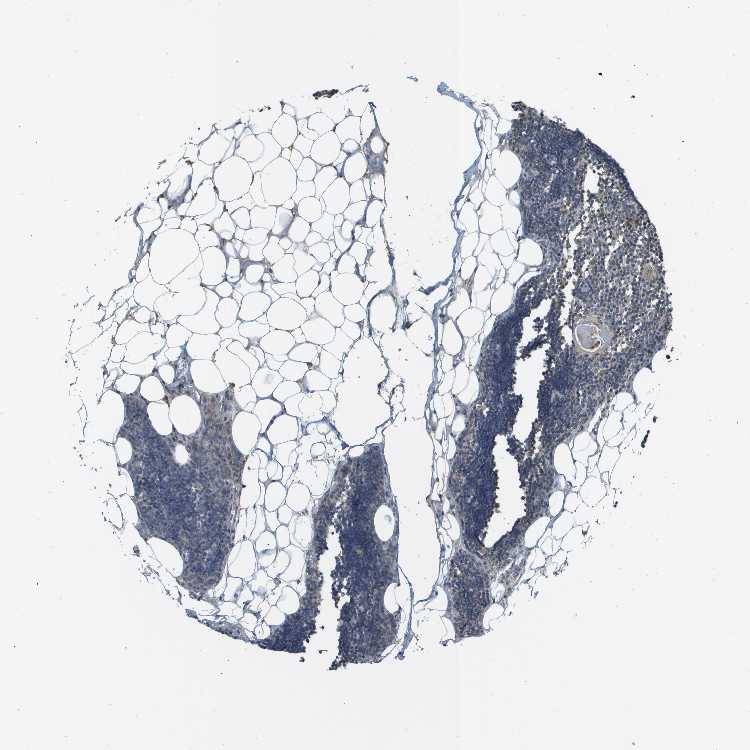

TISSUE PRIMARY DATA LYMPH NODE Show tissue menu

Lymph node

LYMPH NODE - Antibody stainingi

Antibody staining in the annotated cell types in the current human tissue is reported as not detected, low, medium, or high, based on conventional immunohistochemistry profiling in selected tissues. This score is based on the combination of the staining intensity and fraction of stained cells.

Each image is clickable and will lead to virtual microscopy that enables deeper exploration of all samples and also displays staining intensity scores, fraction scores and subcellular localization as well as patient and tissue information for each sample.

Antibody HPA002896Antibody HPA003590Antibody CAB017491

Germinal center cells LowLowNot detected

Non-germinal center cells LowNot detectedLow